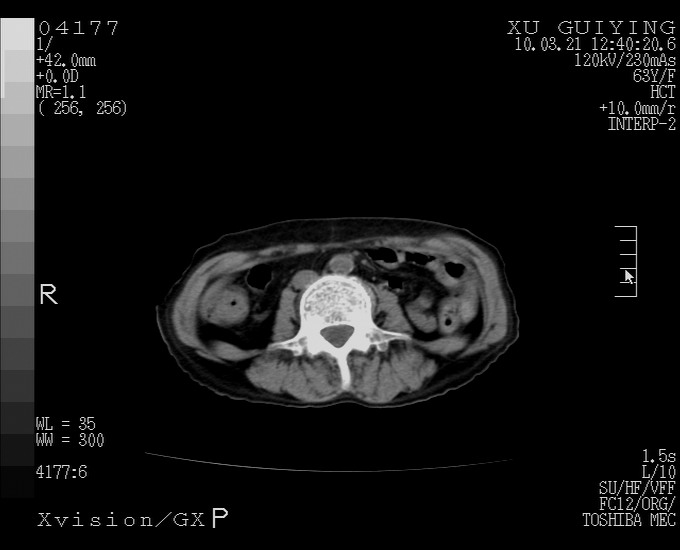

标题: CT25230:女,63岁,萎缩性胃炎病史,患者明显黄染,不能进 [打印本页]

标题: CT25230:女,63岁,萎缩性胃炎病史,患者明显黄染,不能进

怎么没有增强呢?胆囊那么大,密度有些高啊。

慢性胆囊炎,胆囊占位不排除,建议增强或彩超。

考虑胆囊炎 不除外泥沙样结石

胆囊体积增大,胃窦壁增厚

胆囊体积增大,密度不均匀,结石不除外;胃壁增厚,考虑胃癌,建议增强。

胆囊体积增大,密度增高,较均匀,外缘也较光滑,应考虑胆囊炎。因为胃未充盈,不好说壁增厚。肝左叶及脾门处见低密度灶,有可能是血管瘤,不排除囊肿。建议超声检查或强化。